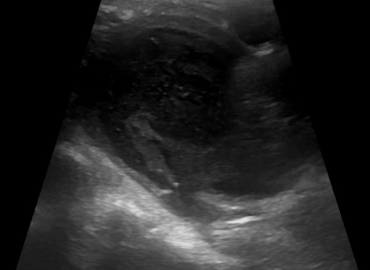

Embarazo de 26,2 semanas. MC Genitorragia